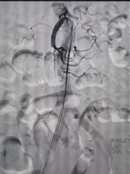

对此,普外科医师团队与多学科开展紧急会诊,并制定出最佳手术方案,决定为患者开展介入手术治疗致命肠系膜上动脉栓塞。在征求患者及家属同意后,普外科团队立即启动“绿色通道”,由副主任医师郭陵主刀,紧急为患者实施介入手术(肠系膜上动脉吸栓+肠系膜上动脉球囊扩张+肠系膜上动脉支架置入术),手术过程顺利。

术中取栓前后肠系膜上动脉造影对比